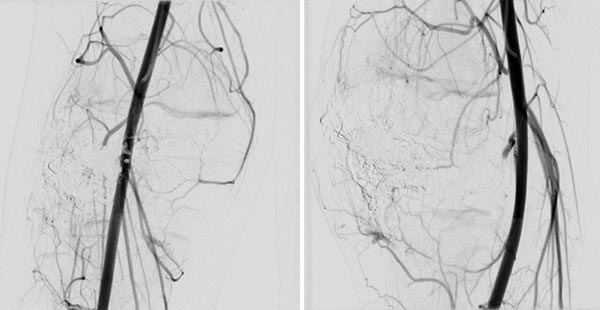

In the control DSA (left AP, right lateral) after embolization with ethylene-vinyl alcohol copolymer, no more perfusion is seen in the angiography even in a long series. The AVM is considered to be occluded.

The repeat DSA 4 months after the previous embolization (left AP, right lateral) shows an early, circumscribed recurrence. Especially in the case of AVMs associated with a PTEN hamartoma syndrome, patients must attend for follow-up at short intervals, as these AVMs in particular have a high tendency to recur.